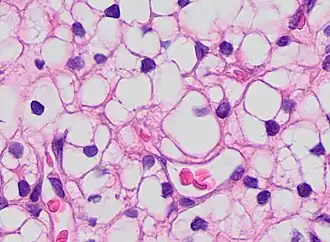

Pleomorphic when having different sizes and shapes. This often correlates with an increased nucleus to cytoplasm ratio. These features generally indicate malignancy.

Pleomorphic when having different sizes and shapes. This often correlates with an increased nucleus to cytoplasm ratio. These features generally indicate malignancy. -